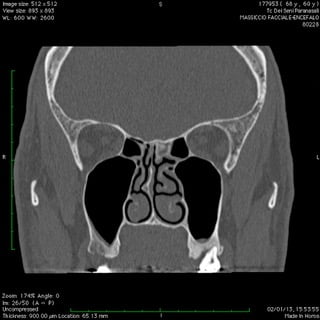

Anche nelle sinusiti la peculiare morfologia anatomica delle strutture coinvolte, cavità ossee, consente nella maggior parte dei casi latenze di esordio molto ritardate rispetto il primitivo insorgere patologico palesandosi così in avanzate fasi di compromissione .

Nelle forme croniche, cioè di malattia stabile nel tempo, i seni paranasali diventano “ siti di decantazione”, ovvero di ristagno e moltiplicazione,per germi di vario genere dando vita così ad un persistente primario serbatoio contaminante sia le vie aeree che quelle digestive.